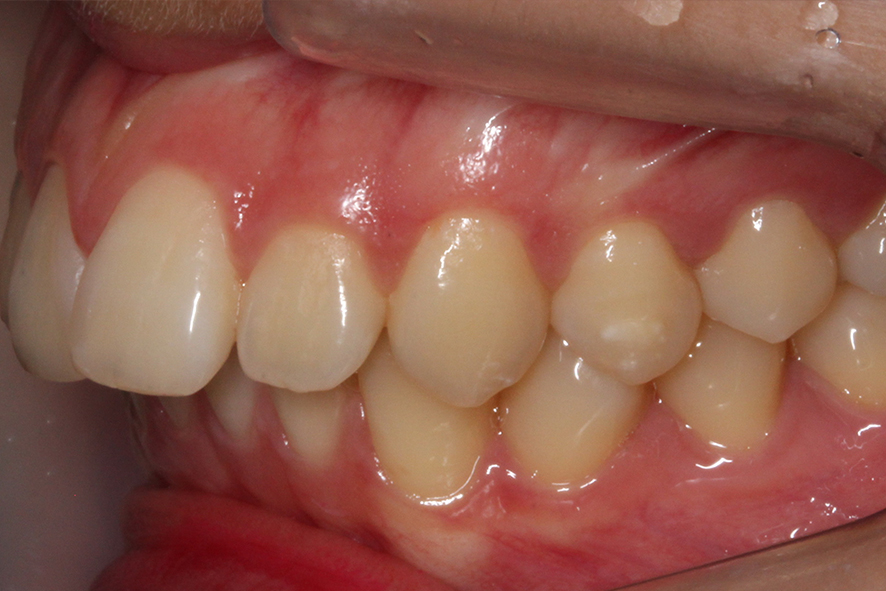

overjet 사진을 보면 돌출감이 심해 보이지

않았던 정면 및 overbite 사진과 달리

상악의 뻐드러짐이 심한 모습인데요,

구치부 교합을 확인해봐야 알겠지만

상악이 과하게 발달한 2급 부정교합

증상이 있을 것으로 보입니다.

이러한 전치부 교합 상태를 가진 분들의 경우

상하악 앞니가 서로 맞닿지 않기 때문에

아래 앞니에 의해 윗니의 설측면이

손상될 가능성이 있습니다.

또한 음식을 드실 때 치아의 절단력을

사용하기 어렵기 때문에 혀를 내밀어

절단하는 경우가 있는데요,

이러한 습관이 지속된다면

치아의 돌출이 더 악화될 가능성이 있습니다.

치아의 교합평면을 보면 구치부의

교합 상태가 정상적인 치아교합과

다른 모습을 확인할 수 있는데요,

상악이 하악보다 앞쪽으로 나와 있어

어금니의 상하악 교합이 어긋난 모습입니다.

반대쪽 교합 평면 또한 상악 악궁의 길이가 길고

과도하게 발달하였기 때문에 어금니의

위치가 앞쪽으로 밀려나듯이 교합되는 모습입니다.